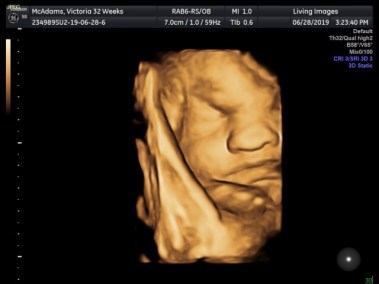

Milestone #6: The 3D Ultrasound

Seeing our little baby in a 3D ultrasound was something I almost gave up, but I am so glad that I didn’t. On this day, my husband found out that he had to work later than he was originally told, and our ultrasound appointment was over an hour away. I hopped in the car and sped over to the appointment, calling my mother to meet me there, and tried to convince myself to not feel bad about my husband being unable to join. As I laid on the table watching the ultrasound technician find my son’s most prominent features, I was overwhelmed with such excitement and joy. Our cantelope-sized little guy was sleeping so soundly and couldn’t be wakened. Out of the entire hour that I spent watching my baby sleep, we were able to get three half-decent photos of him with his fist laying slightly under his head. He was sleeping so very soundly, and he was incredibly beautiful.